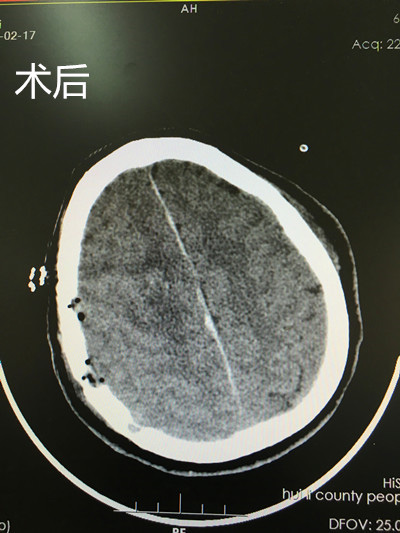

前不久,自贡市三医院对口支援会理县医疗队挂职副院长、硕士研究生、神经外科主治医师张诚,帮助会理县医院成功实施了首例颅内巨大肿瘤切除术,填补了该院脑肿瘤手术的空白。

该患者是一名47岁的女性,因反复头痛、左侧肢体无力、麻木1周入院,行头颅CT示:右侧额叶占位病变,约5*5cm,强化提示肿瘤呈均匀强化,血供丰富,需手术治疗。但患者脑肿瘤巨大、血供丰富,位于功能区及窦镰旁,术中大出血及术后左侧肢体偏瘫的可能性极大,且缺乏头颅MRI和手术开颅动力装置,手术条件相对简陋,目前仅开展了常规颅脑外伤及脑出血手术,未开展脑肿瘤手术,既往此类患者均需转攀枝花或者西昌治疗,因而手术难度和风险较大。张诚医师急患者所急、想患者所想,经反复向患者家属沟通和充分的术前准备,凭借扎实的理论功底、娴熟的操作技能,在相关人员的密切配合下,主刀行右侧额叶占位病变切除术,历时6小时成功全切肿瘤,这也是该院神经外科首例脑肿瘤手术。术后患者一般情况良好,受到患者家属和医院领导及同行的好评。